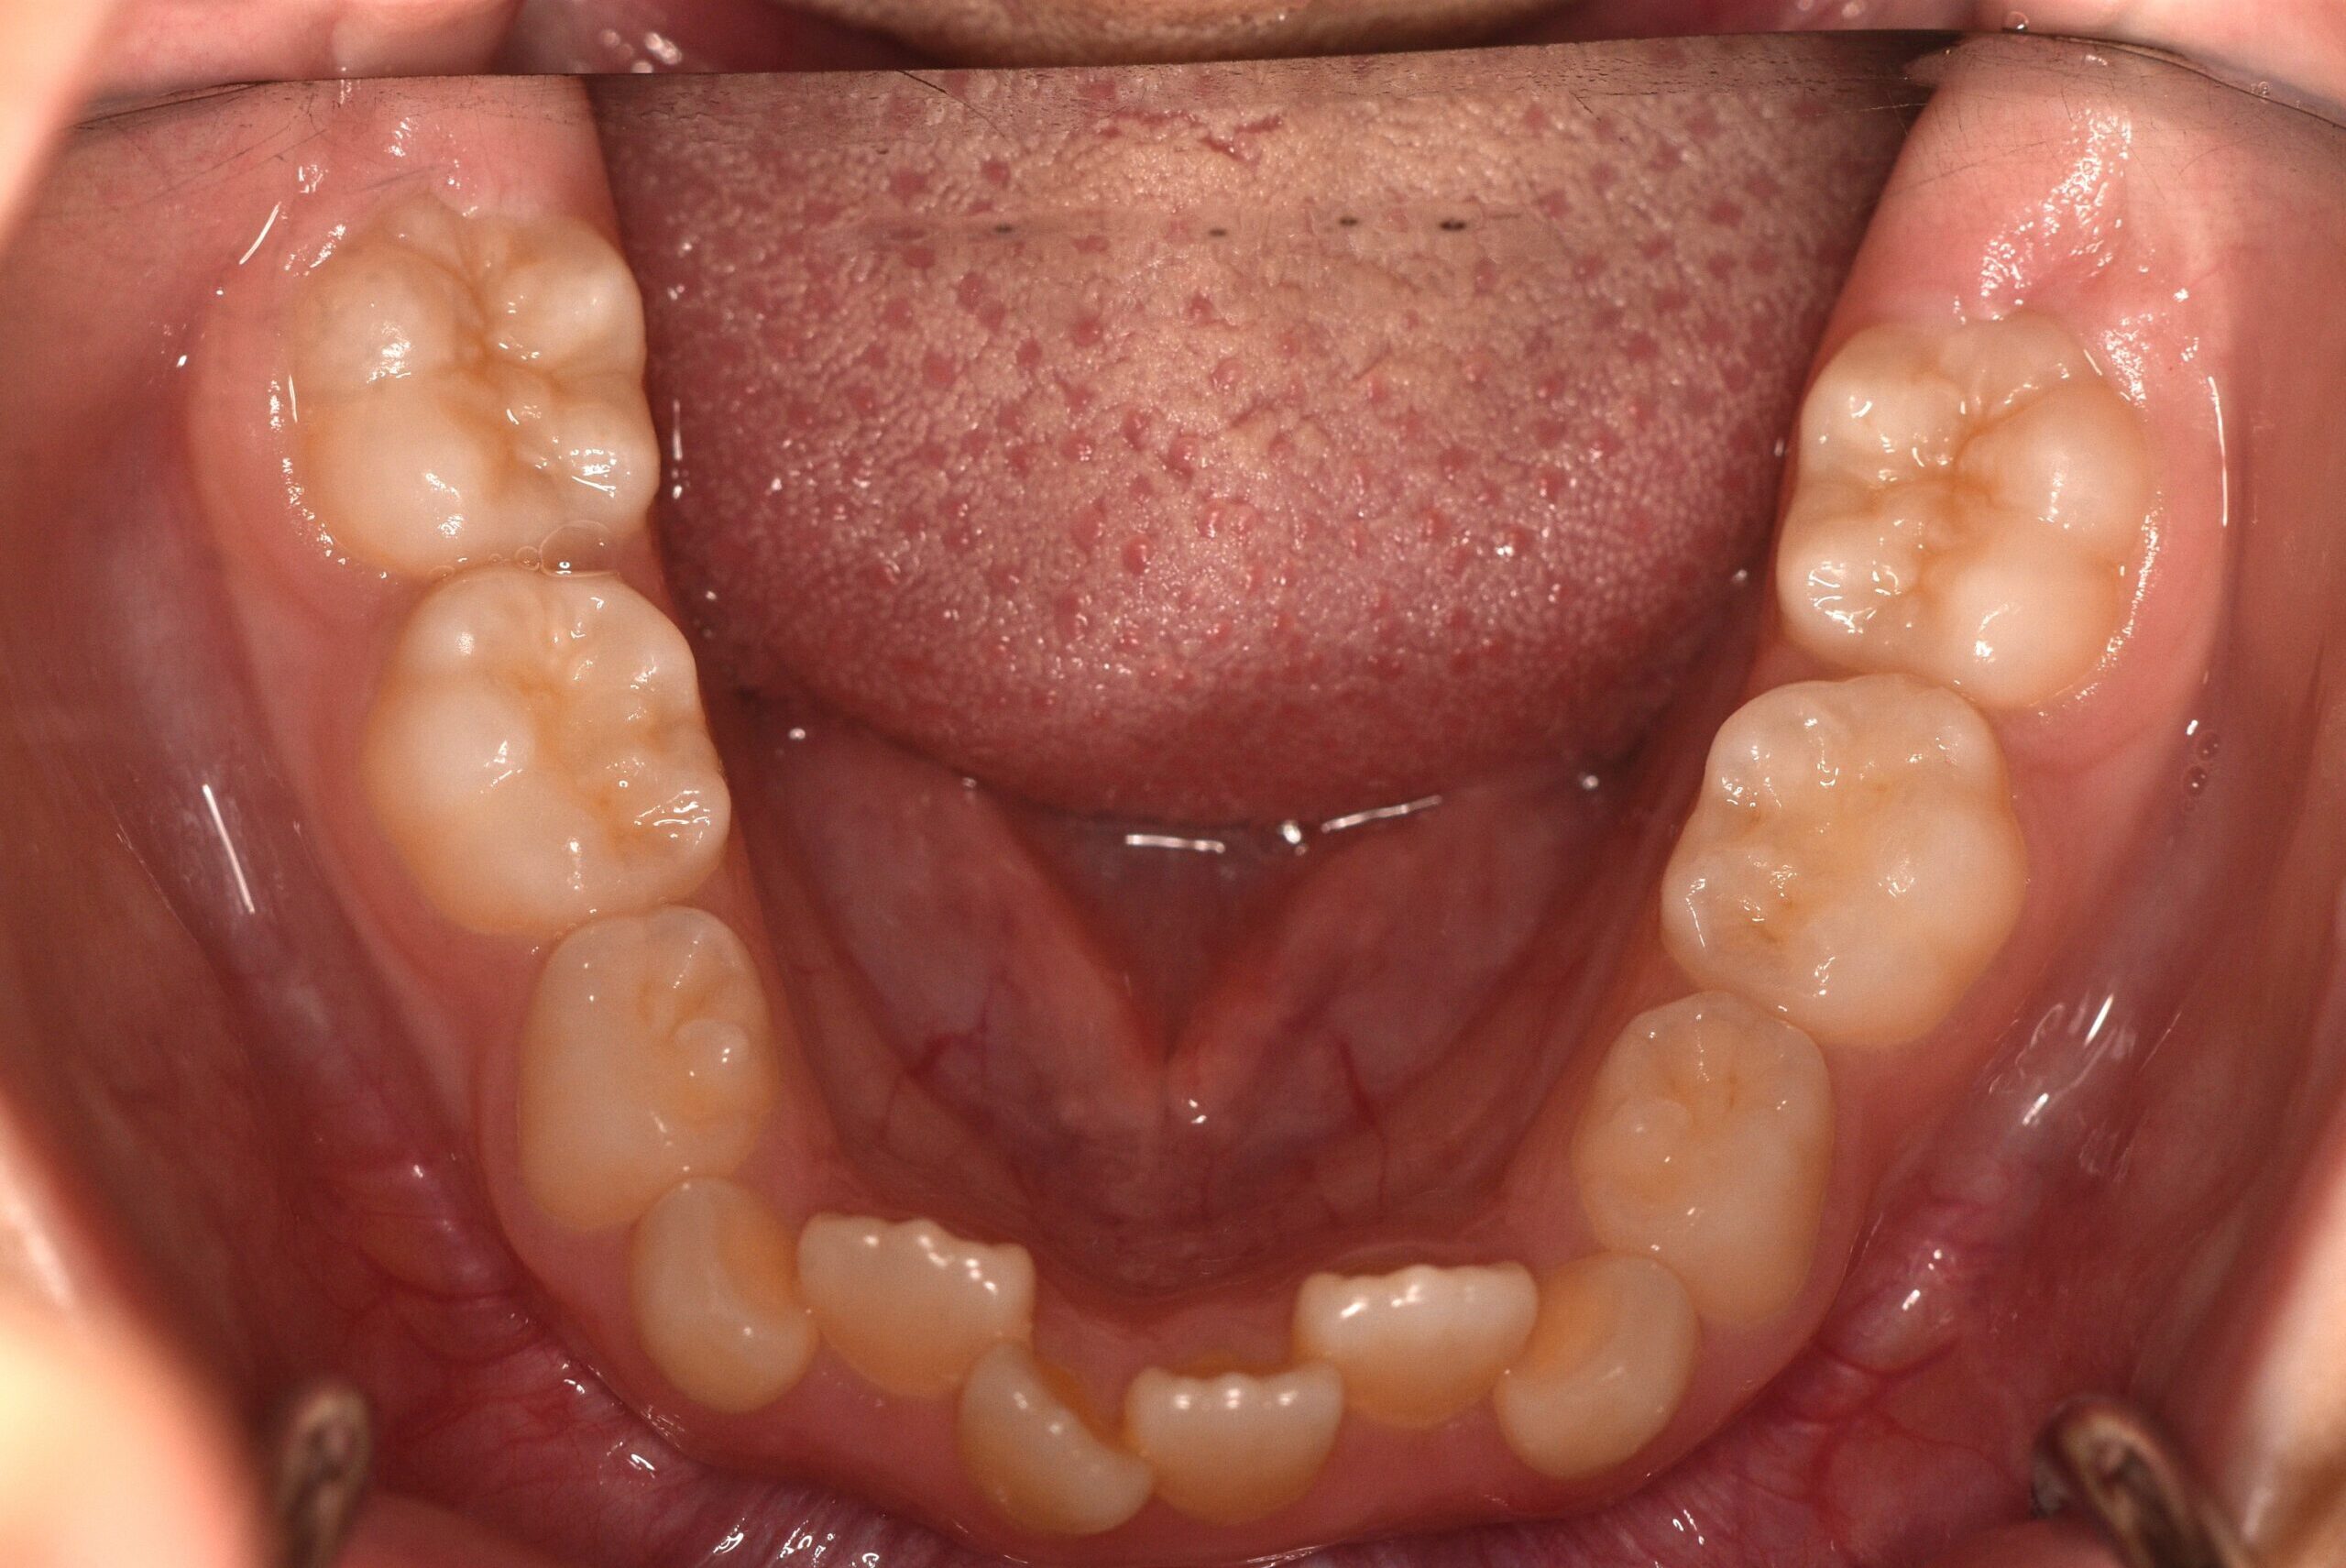

初診時

年齢

9歳 性 別 女性

治療期間 7ヶ月 費 用 矯正施術料:800,000円

調整料:4,000円/月

治療内容の詳細 初診時9歳の女児で、歯のがたつきを気にされ来院されました。

検査の結果、前歯部叢生を伴うアングルⅠ級不正咬合と診断しました。

治療としてはマウスピース矯正(インビザラインファースト)で配列を行い、上下顎の側方拡大と萌出スペースを確保しました。

治療期間は、7ヶ月でした。

今後、側方歯生え変わりまで経過観察を行います。